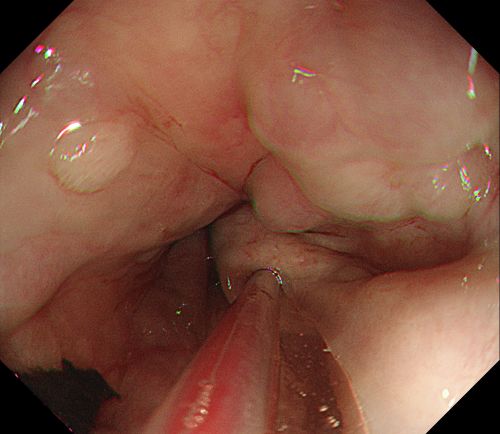

内镜下可见重度食管静脉曲张,且有较多血凝块。

为其实施内镜下食管静脉曲张套扎术。

患者旋即被推入手术室,麻醉三科刘际童主任为其进行气管插管、全麻,保持呼吸道通畅,并进行中心静脉置管等维持血压平稳。综合内科彭娅主任进行胃镜治疗,发现患者重度食管静脉曲张,胃底可见大量血液及血凝块;小心翼翼抽吸血液及清洗血块后,寻找到“犯罪血管”,在内镜下进行食管静脉曲张套扎+硬化剂注射治疗,封闭出血血管。